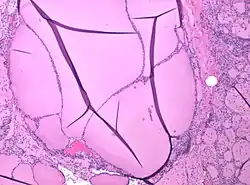

Colloid nodules are distinguished by an apparently gelatinous mass of colloid both surrounding and contained within follicular cells. Colloid nodules are not surrounded by a fibrous capsule of compressed tissue. However, they are surrounded by flattened epithelial cells.[8] Both the number of cells and the type of colloid may vary considerably.[7]